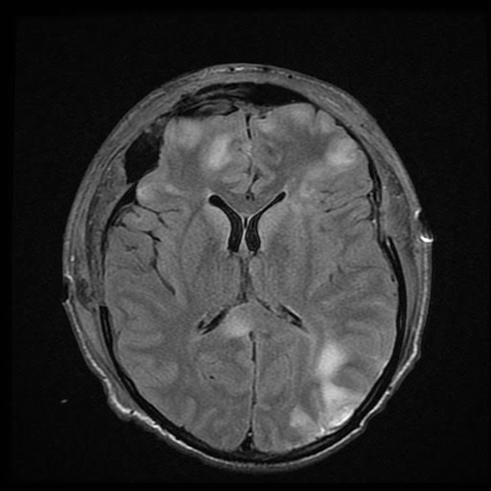

Fig. 19.5

T2 FLAIR sequence 1 month after accident showing signal intensity within the right parieto-occipital, bifrontal, and splenium consistent with diffuse axonal injury

A 21-year-old male was involved in a T-bone collision while riding a motorcycle wearing a full face helmet. He was a GCS 3T on arrival to the hospital. His head injuries involved a left parieto-occipital contrecoup contusion and subtle bifrontal hypodensities and multiple orthopedic injuries. An EVD was placed and his intracranial pressures were managed medically for the first 5 days. Eventually the right parieto-occipital contusion and bifrontal hypodensities evolved causing 5 mm of left to right midline shift and medically refractory elevated ICPs > 20 mmHg. A wide bifrontal craniectomy was performed. He developed bilateral subdural hygromas 2 weeks after surgery that resolved spontaneously after 3 days of observation. He underwent a bifrontal cranioplasty 4 months after the craniectomy. He was discharged to neuro-rehab with a GCS 14. He has moderate cognitive changes and emotional lability consistent with his frontal lobe injury.